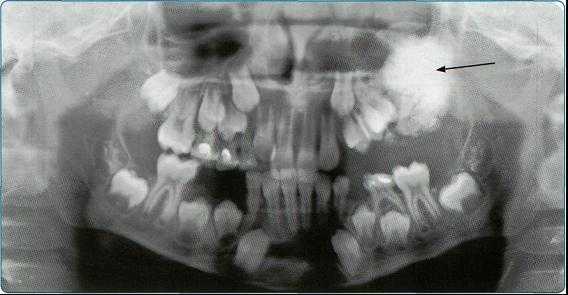

Основной методикой рентгеновского исследования челюстно-лицевой области является ортопантомография (ОПТГ), которая совершенствуется, переходя на цифровой способ получения изображения. На ОПТГ отображается панорамный рентгеновский снимок зубочелюстной системы пациента, на котором видны верхняя и нижняя челюсти, развёрнутые в плоскости, корни, каналы зубов, имеющиеся имплантаты, ортопедические конструкции, пломбы, а также пародонтальные щели, гайморовы пазухи, носовые

ходы, височно-нижнечелюстные суставы, нижнечелюстной канал.

Методика оправдана для предварительных скрининговых исследований широких масс населения, поэтому активно используется при диспансеризации. Ортопантомография превосходит стандартные рентгеновские снимки и позволяет дифференцировать кисты одонтогенного и риногенного происхождения, оценивать окружающие структуры лицевого отдела головы. Однако ОПТГ имеет ряд ограничений — изображение является плоскостным, что не дает возможности оценить распространение кистозного процесса и состояние окружающих структур, а также не в полной мере дает информацию о состоянии корневых каналов.

На основании панорамных снимков диагностируют кариес и его осложнения, кисты разных типов, новообразования, повреждения челюстных костей и зубов, воспалительные и системные поражения. У детей хорошо определяется состояние и положение зачатков зубов.

Ортопантомограммы демонстрируют взаимоотношения зубов верхнего ряда с дном верхнечелюстных пазух и позволяют выявить в нижних отделах пазух патологические изменения одонтогенного генеза.

Особенно важно использовать ортопантомографию в детской стоматологии, где она не имеет конкурентов в связи с низкими дозами облучения и большим объемом получаемой информации. В детской практике ортопантомография помогает диагностировать переломы, опухоли, остеомиелит, кариес, периодонтиты, кисты, определять особенности прорезывания зубов и положение зачатков.